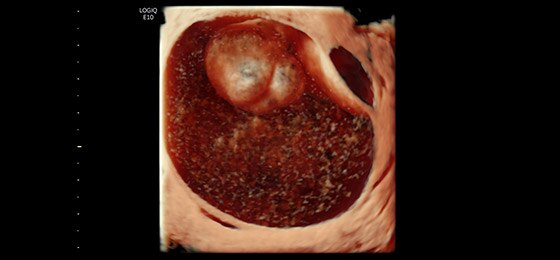

Ovarian Mass 3D Render with HDlive™, RIC5-9-D